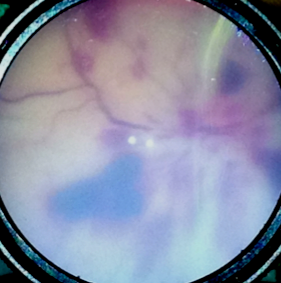

A chapter Squier co-authored with radiologist Julie Mack examines the imaging of the most common brain findings in SBS/AHT cases, with commentary on what isn’t yet understood and the limitations of what imaging can reveal.